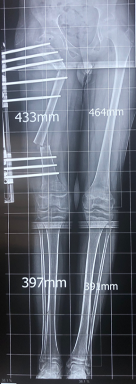

El tratamiento de la Pseudoartrosis Congénita de Tibia y Peroné (PCTyP) ha sido diverso. Todas las técnicas de tratamiento tienen una cuota de complicaciones, pero es la re-fractura y la falta de unión las principales consecuencias que se desean evitar. El objetivo de esta investigación se basa en analizar las técnicas quirúrgicas empleadas en nuestro centro y determinar los resultados. Se realizó un estudio retrospectivo, donde se estudiaron 11 pacientes con esta enfermedad con un seguimiento promedio de 4,73 años (DS±4,56). Todos los pacientes en quienes se utilizó la técnica de Charnley-Williams (CW) lograron la consolidación, la protección del clavo funcionó hasta que el extremo proximal de la tibia queda desprotegido al crecer el hueso y se produjeron angulaciones en esta zona, usualmente en la tibia proximal. Con el uso del clavo endomedular (EM) telescópico de Fassier-Duval (FD) se logra la protección de todo el hueso, inclusive durante el crecimiento. Se concluye que la técnica de CW es un buen método para la resolución de esta enfermedad y con el uso del clavo EM de FD se evita la refractura y se logra la unión permanente a medida que continúa el crecimiento del hueso. La discrepancia de los miembros inferiores es debida a la afectación de la tibia que compromete su crecimiento normal.